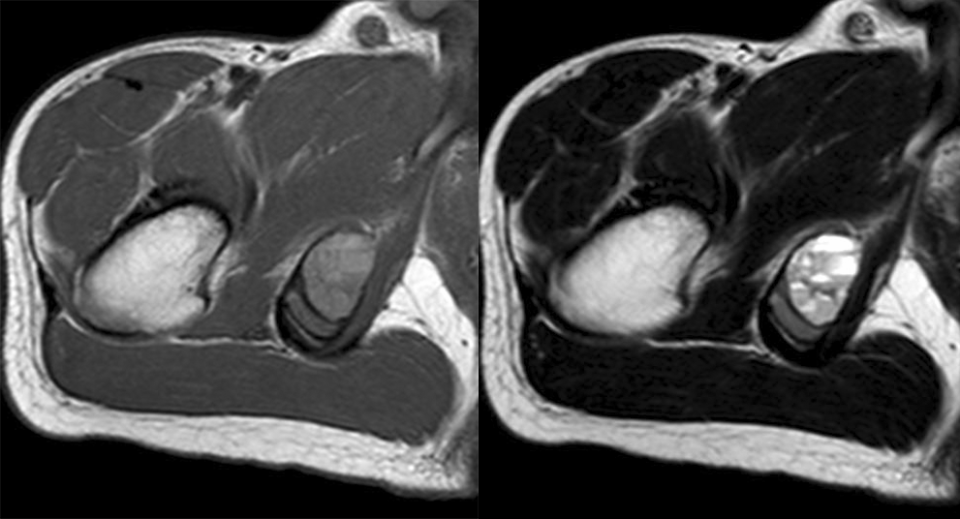

No.9

瘤周水肿

肿瘤周边的骨髓水肿表现为 T1WT 低信号和 T2WI、STIR 高信号边界模糊的片状影,软组织肿块邻近的正常软组织成分,尤其是肌肉内亦可出现水肿,表现为肿块周围沿肌束方向分布的边界模糊的片状或羽毛状影,有时可连成片。瘤周水肿常见于恶性肿瘤(图 58),但也可见于某些良性肿瘤如软骨母细胞瘤(图 59)、骨样骨瘤和骨嗜酸性肉芽肿(图 60)等。

图片

图 58.瘤周水肿:骨肉瘤

图 59.瘤周水肿:软骨母细胞瘤

图 60. 瘤周水肿:骨嗜酸性肉芽肿